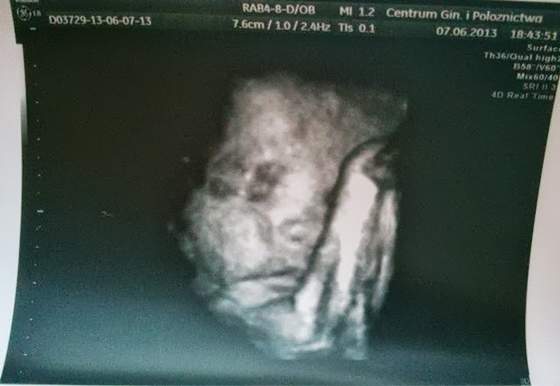

My już po usg :)...

Malutka jest zdrowiutka i nadal jest Amelką :tak:

DSC_0215aa.jpg

• DSC_0215aa.jpg

17,8 KB · Wyświetleń: 56